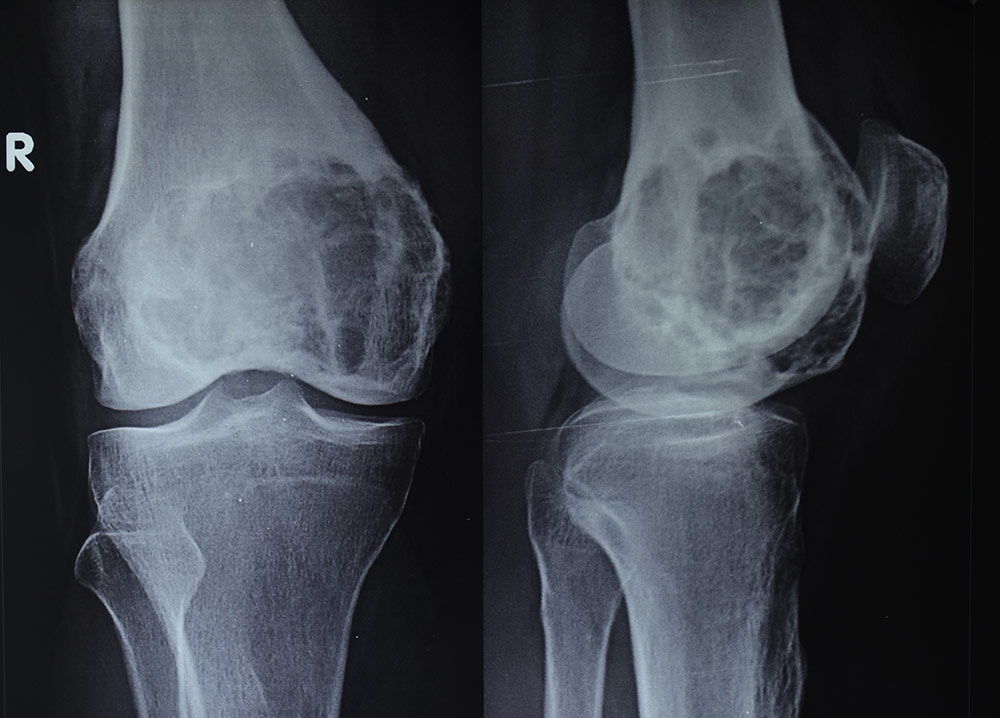

Остеосаркома коленного сустава: информация и поддержка